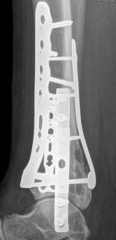

Removal of implants is not mandatory but recommended if implants are prominent under the subcutaneous envelope of the distal tibia. Implant removal should be undertaken only after healing is complete, ie, after 1 year at the earliest. This patient had achieved good radiographic and functional healing at the 1-year postoperative review (Fig 2.2-8 and Fig 2.2-9).

Fig 2.2-8a–b Postoperative x-rays at 1 year showing healed fractures, implants in situ, and limited tibiotalar arthrosis.

1. AP view.

2. Lateral view.